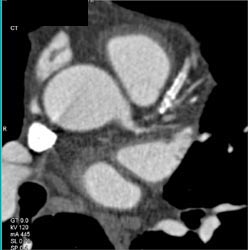

Significant Calcification of LAD and Circumflex Artery (CX)